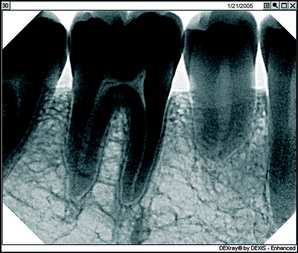

First, there's the critical matter of diagnostic capability. I don't care what other dentists might say who are still trying to convince themselves they should stick with film technology, you can improve your diagnostic capability significantly using digital radiography. With digital, you're looking at an image that fills a 19-inch computer screen and not a film image the size of a postage stamp. Using the software-based digital radiography's image enhancement functions such as magnification, brightness control, and heightened contrast, you can bring out aspects of the X-ray that simply aren't visible on film, including such things as tiny fractures and imperfections that you might very well miss on film. Once you begin to practice using magnification for vision, you wouldn’t practice without it. It’s the same with the digital x-rays.